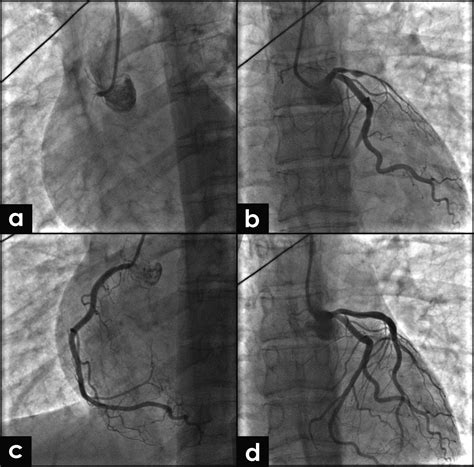

Illustration of a coronary artery undergoing a spasm

• Coronary Angiography: A procedure where a doctor injects a dye into the coronary arteries to visualize flow. If a spasm is suspected, a doctor might administer a medication (like acetylcholine) during the procedure to safely provoke a spasm under controlled conditions.